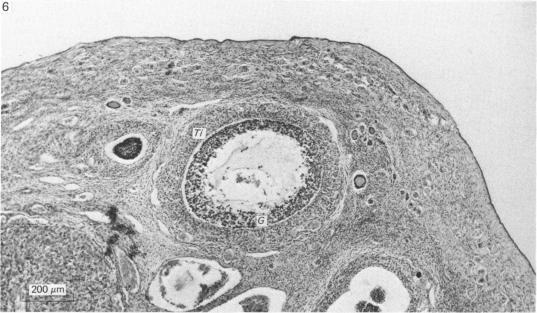

The ovarian morphology and the pattern of follicular development and atresia have been described for the dusky leaf monkey, Presbytis obscura, on the basis of a study of material from 44 female monkeys collected at various stages of the menstrual cycle, pregnancy and lactation. Marked differences were found in the dimensions of many ovarian components between this monkey and the other species of langur previously described. During follicular development the oocyte increased in diameter from 28 micrometer in the primordial follicle to a maximum of 85 micrometer in a pre-ovulatory follicle measuring 8.0 x 4.0 x 7.0 mm. The majority of developing follicles, however, underwent atresia with the theca interna transforming into interstitial tissue. Although present in the follicular phase of the menstrual cycle, this tissue was most pronounced during early pregnancy, at a time when lutealisation also occurred, resulting in the formation of corpora lutea atretica. These findings have been discussed in relation to other catarrhine primates.

基于对44只处于月经周期、怀孕和哺乳期不同阶段的雌性叶猴的研究材料,已对黑叶猴(Presbytis obscura)的卵巢形态、卵泡发育和闭锁模式进行了描述。在该叶猴与先前描述的其他叶猴物种之间,发现许多卵巢成分的尺寸存在明显差异。在卵泡发育过程中,卵母细胞直径从原始卵泡中的28微米增加到排卵前卵泡(直径8.0×4.0×7.0毫米)中的最大85微米。然而,大多数发育中的卵泡会发生闭锁,卵泡内膜转化为间质组织。尽管该组织存在于月经周期的卵泡期,但在妊娠早期最为明显,此时也会发生黄体化,导致闭锁黄体的形成。已结合其他狭鼻猴灵长类动物对这些发现进行了讨论。